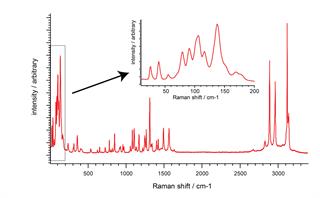

One spectrum reveals all

Save time. Use SynchroScan to reveal all the key Raman bands; at high spectral resolution, over the entire Raman range, in just one data collection. See lattice modes, OH bands, and everything in-between. Spot the most subtle sample differences wherever they occur in the spectrum.